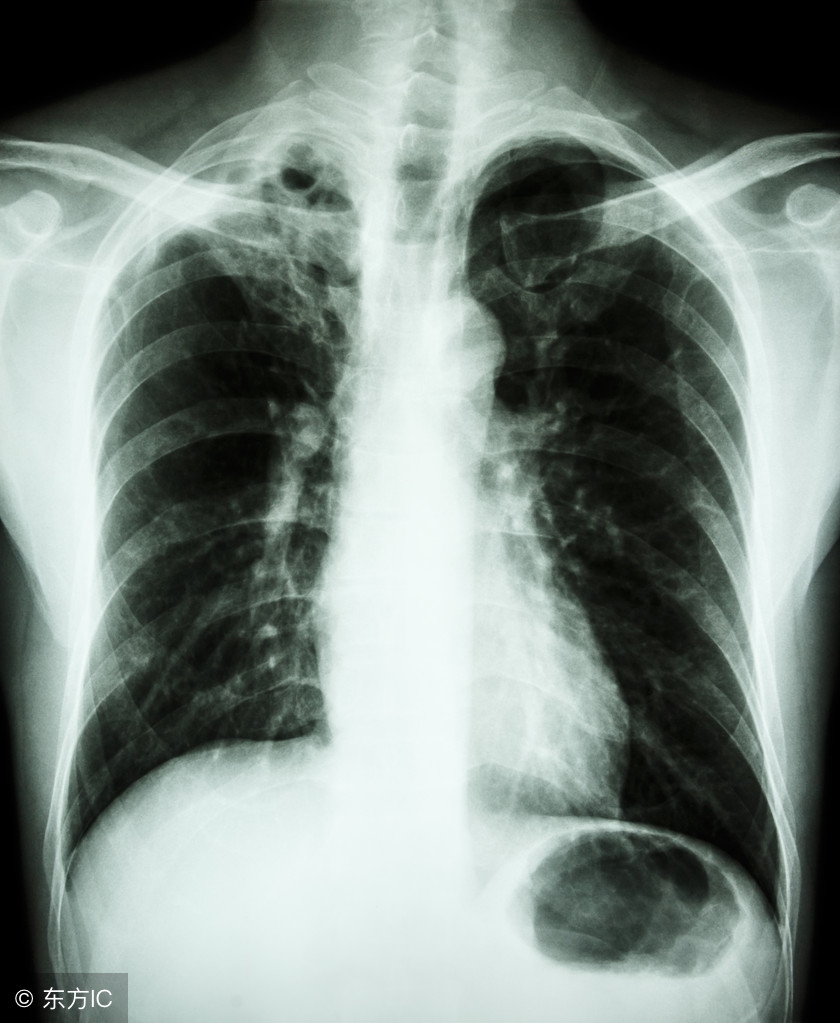

大家都知道肺结核对身体健康的危害较大,特别是肺部,会造成永久性损伤,肺结核肺部有空洞就是损伤的一种,那么肺结核肺部有空洞是怎么回事呢?

对于抵抗力较差的人来说,更易感染结核杆菌。当感染肺结核之后,结核杆菌会侵害我们的肺部,导致肺部出现空洞,可在肺部ct中发现。

肺结核是由于结核杆菌感染所致,结核杆菌会对肺部细胞产生损害形成结核病灶,由增生的疤痕和肉芽肿组织取代损伤的肺部细胞。而大家所说的肺结核肺部有空洞就是结核杆菌病灶治愈后所形成的干酪样坏死,形成空洞。